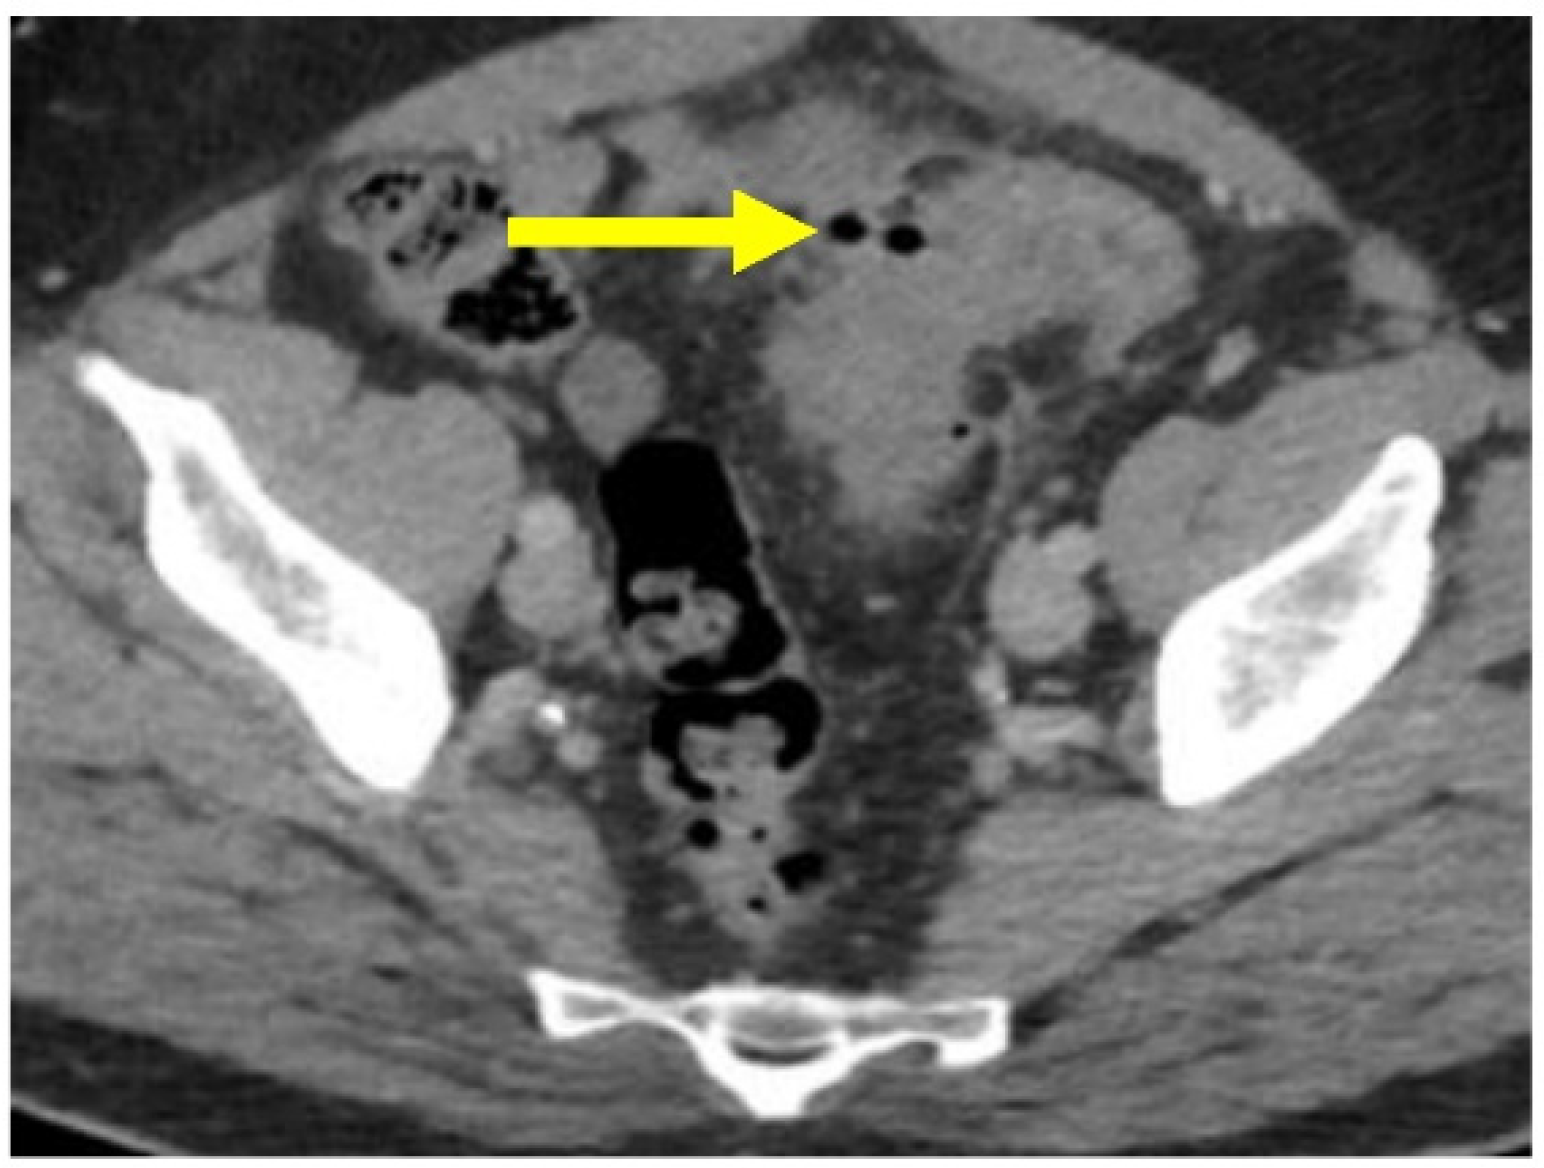

Figure 6.

Microperforation. Axial CT image through the pelvis with IV contrast. There is a small amount of extraluminal air (yellow arrow) along the medial wall of the sigmoid colon, without evidence for abscess. There is adjacent inflammation related to acute diverticulitis.

CT scanning can show complicated disease as a peridiverticular mesenteric inflammatory reaction (Hinchey Ib) or microperforation with adjacent extraluminal air (Figure 6). Contrast is also helpful to evaluate for potential abscess (Hinchey Ia or II), where rim-enhancement will be seen (Figure 5).